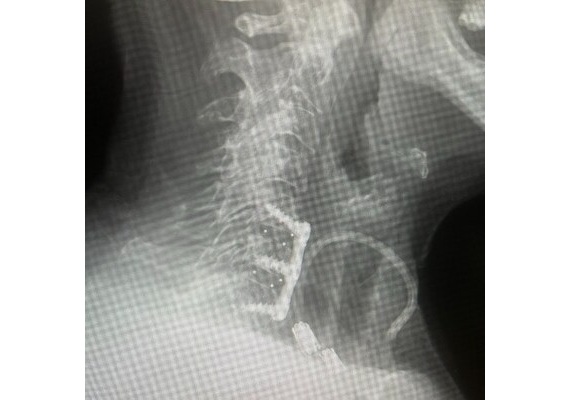

2-level ACDF with NanoPrime® Labyrinth®